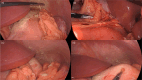

We report the first pediatric use of a laparoscopic-assisted endoscopic overstitch technique for managing an acutely perforated gastric ulcer in a 16-year-old female. The patient presented with symptoms consistent with gastrointestinal perforation, confirmed by radiologic pneumoperitoneum. Diagnostic laparoscopy identified inflammatory adhesions and a gastric ulcer perforation. Concurrent endoscopy precisely located the defect, which was effectively closed using an endoscopic overstitch device mounted on a therapeutic double-channel gastroscope. Closure involved three full-thickness inverted figure-of-eight sutures, verified by an intraoperative leak test and reinforced with an omental patch. Postoperative recovery was rapid and uncomplicated, progressing to a regular diet within 3 days. This innovative hybrid laparoscopic-endoscopic technique demonstrates efficacy, safety, and the benefits of minimally invasive surgery for pediatric gastrointestinal perforations, emphasizing its potential superiority over traditional methods.